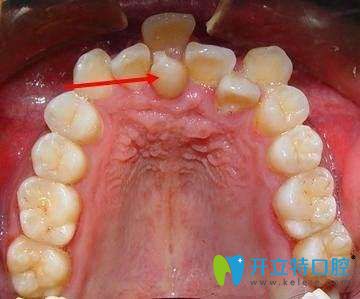

牙齒不齊的圖片

1、影響顧客口腔功能的正常發(fā)揮。降低牙齒的咀嚼效率,還會導致消化不良及腸胃疾病;一些錯合,還會影響正常的發(fā)音及語言表達;

2、影響牙周組織健康及口腔衛(wèi)生。牙列不齊會使口腔菌斑易于附著,牙刷也難以接觸,導致牙齦出血、腫脹、口腔異味等癥狀;久而久之還會累及牙槽骨,出現(xiàn)牙齒松動。

3、影響面部生長發(fā)育及美觀牙齒。通俗地講,正常發(fā)育排列的牙齒,對頜面部高度、深度及寬度的正常生長,有著類似于“支架”的作用。

4、影響心理健康。由于牙列不齊造成的顏面部形象損害,對青少年顧客的心理也會產(chǎn)生影響。